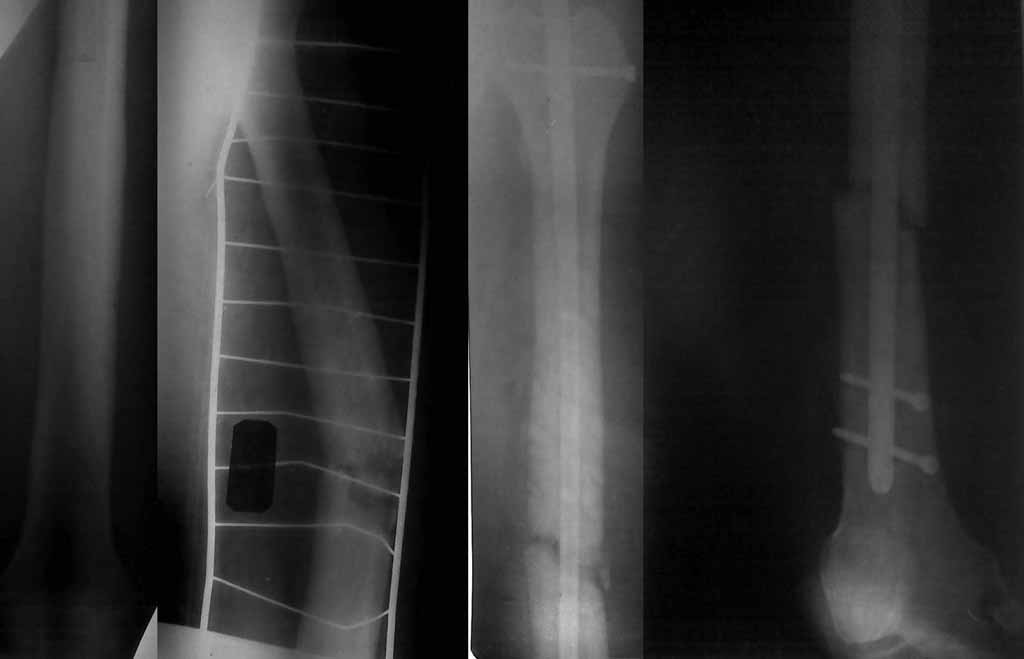

Re: Патологический перелом бедра

Здравствуйте, коллеги. Досылаю рентгенограммы, качество низкое, извините.